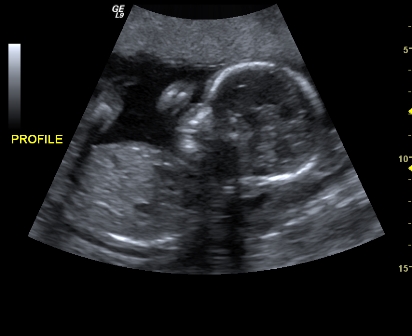

Lili élete első fényképén a gyönyörű kis bantu-néger orrával.

Ez pedig 2-3 hete készült róla. Kaja végeztével fülig ér a szája.